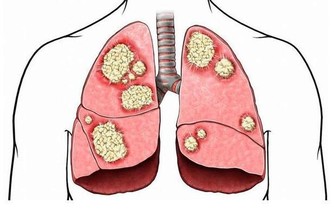

2.凌晨四點醒----肺經問題

凌晨4點是肺部功能最強的時候,異常的話凌晨4點就會醒來。

解決方法:按摩魚際穴、孔最穴等肺經穴位,每次按摩5-10分鐘左右,連續10天,就能通肺經。